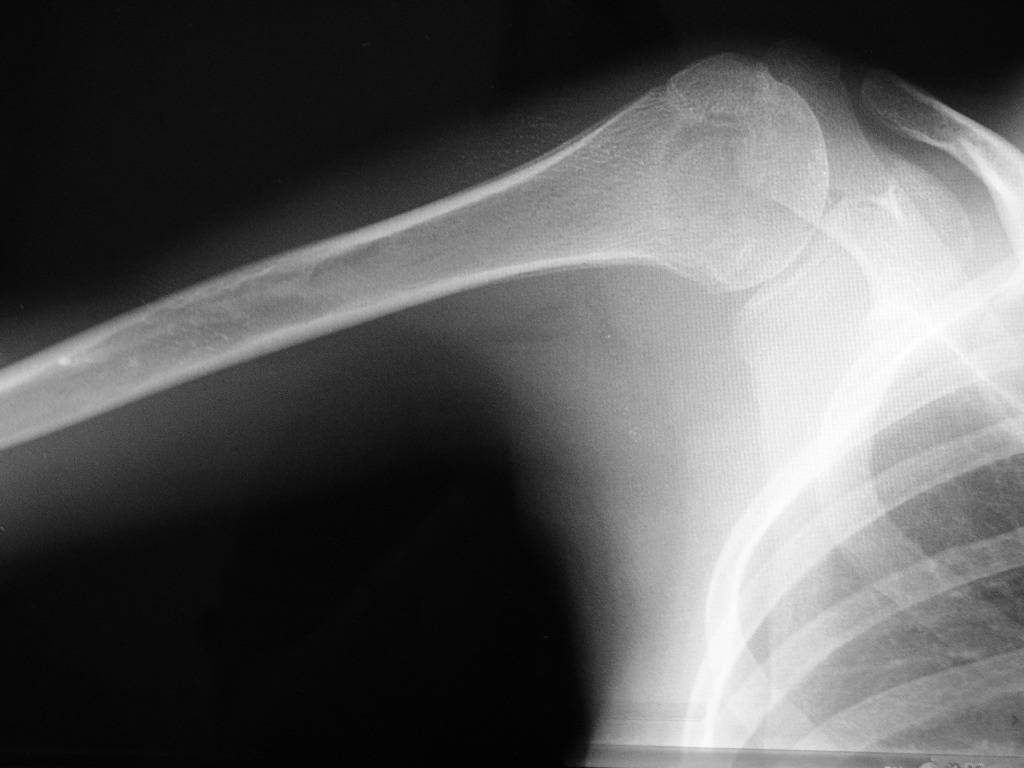

Здравствуйте уважаемые коллеги. Прошу помочь определится с диагнозом. Девушка 16 лет, в течении 10 мес. беспокоят боли в правом плечевом суставе. Последних два месяца возникло резкое ограничение подвижности в суставе. Со слов больной и родителей месяц назад проходила курс лечения у травматолога с диагнозом "периартрит". На момент осмотра плечо отведено до 40 град., активные и пассивные движения резко ограничены, болезненны. Кожные покровы не изменены, пальпация сустава болезненна, общ. ан. крови - норма. Снимки прилагаю. Заранее благодарен за помощь.

Громадный очаг деструкции в головке плечевой кости, резко сужена суставная щель. Для уточнения - вторая проекция, КТ.

У девочки Lytic lesion в головке плеча. Lesion довольно агресивный. Нет четкой границы. Есть периостальная реакция.

очаг деструкции, с достаточно четким контуром, занимающий 75% эпиметафиза плечевой кости, прерывающий кортикальный слой по внутренней поверхности, с периостальной реакцией, у девушки 16 лет - наиболее вероятно, что это гигантоклеточная опухоль с признаками малигнизации.